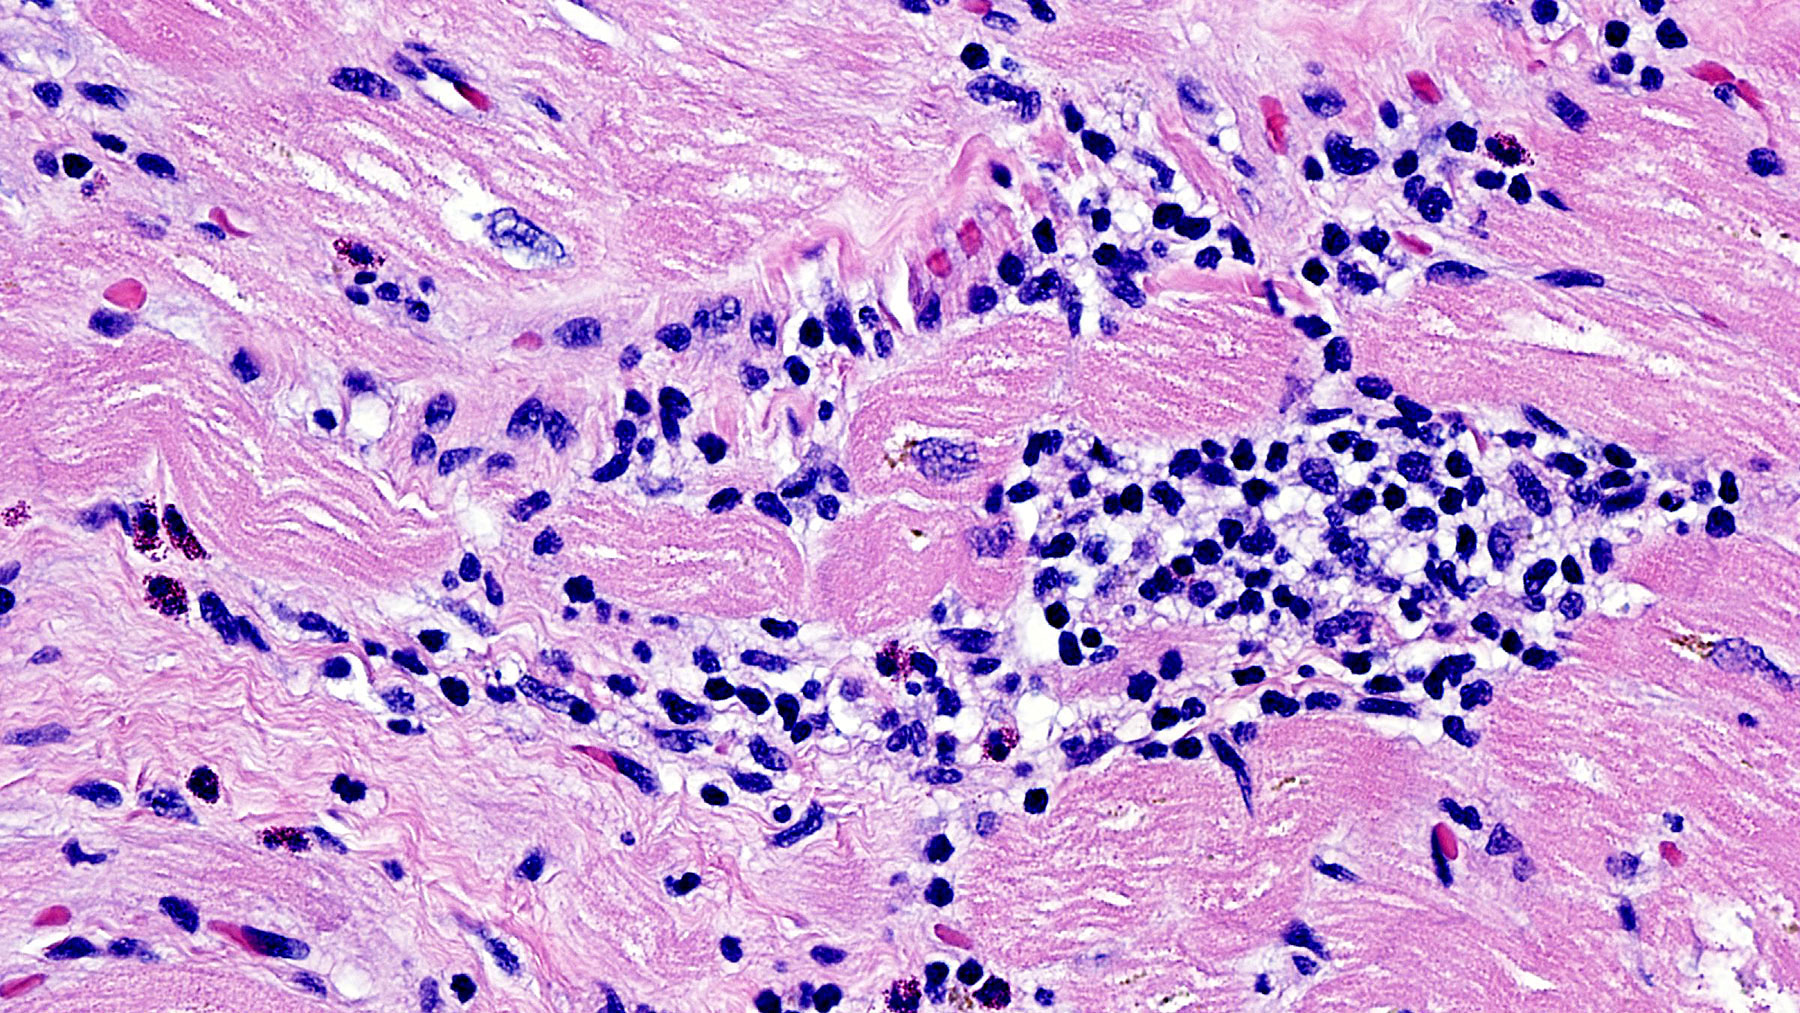

Figure B: H&E staining (20x)

Clinical History: 29 year-old male with history of ulcerative colitis and drug induced lupus developed acute systolic heart failure.

Histology: H&E stains ( Figures A, B, C, and D) show Chronic interstitial myocarditis with mild to moderate infiltration of interstitial spaces with mononuclear cells admixed with scattered eosinophils and diffuse fibrosis.